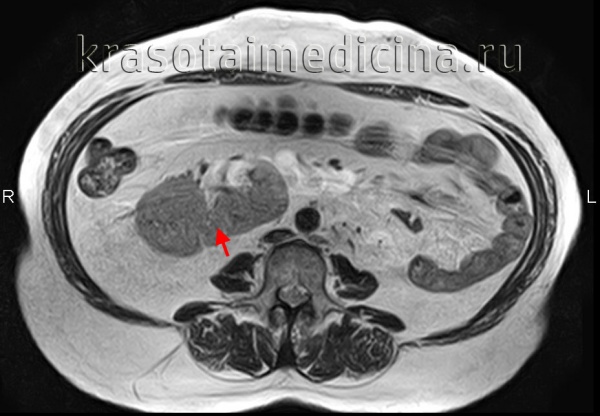

МРТ почек. Аксиальная Т2-ВИ. Подковообразная почка.

Подковообразная почка встречается чаще других и представляет собой увеличение одного из полюсов почки, в 90% – нижнего. Нередко меняется и положение подковообразной почки, которая может быть смещена медиально или даже на противоположную сторону. Подковообразная почка видна при любом виде исследования – внутривенной урографии , УЗИ, КТ, МРТ почек или сцинтиграфии.